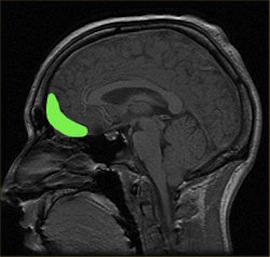

Some people are hard-wired to be addicts even before they touch alcohol or drugs, according to the findings of a recent study of teenage brains. In the largest brain-imaging study ever performed, scientists at the University of Vermont made MRI scans of the brains of 1,900 14-year-olds, while asking them to perform repetitive tasks and then stop mid-way through. (The same test, when used to measure inhibitory control in adults, has found that people who abuse drugs and alcohol generally perform poorly.) The scientists were able to isolate one area of the brain—the “orbitofrontal cortex”—that’s responsible for impulse control. The teenagers with less MRI-indicated functionality in this region showed poorer impulse control—and these teens were more prone to early experimentation with alcohol, cigarettes and illegal drugs. “These networks are not working as well for some kids as for others,” says study leader Dr. Robert Whelan. His co-researcher Hugh Garavan notes, “The differences in these networks seem to precede drug use.” So these findings suggests the possibility of identifying addictive tendencies early on, simply by looking at someone’s brain. “While identifying those at greatest risk of addiction is a complex process with many different factors involved, identifying brain networks specific to impulse control represents the first step,” says Whelan. Previous research on young people suggests that addictive behaviors tend to kick in early; more than 15% of teenagers meet the criteria for substance abuse by age 18.